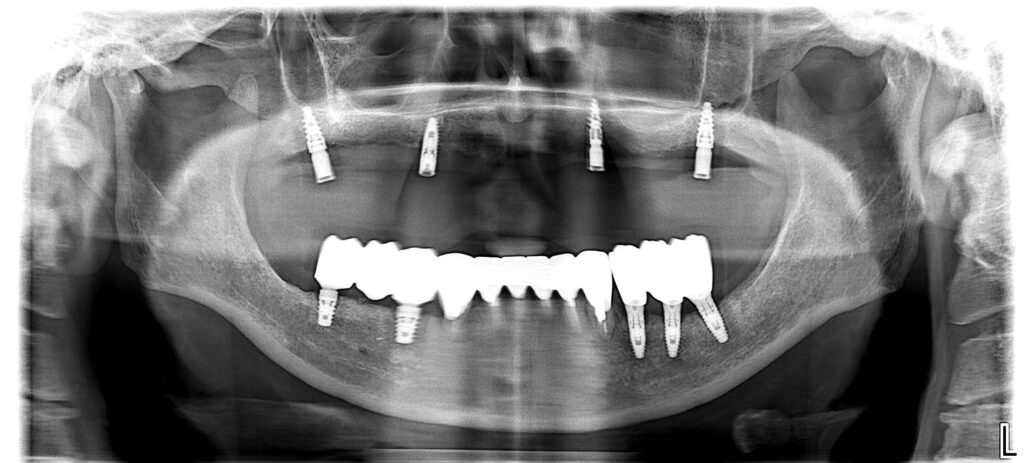

[症例4]

他院にてインプラント治療を行うが、上顎は4本中2本が脱落し、残りの2本のうち1本も膿が出て動揺している。

下顎は右下(向かって左下)3本のインプラントが脱落し、骨の吸収のため最埋入が出来ず、残りの歯を削ってオーバーデンチャー(歯とインプラントの上から被せる義歯)が装着されているが、うまく噛めない上に患者は見た目に不満を持っている。

当院では上顎は前医で埋入した1本のインプラントは保存し、上顎洞に骨を作って新たに3本のインプラントを埋入し、インプラントで支える面積を小さくした総義歯を作成した。

下顎は骨の足りなくなった右下に垂直的に骨を増やし、神経を損傷しないようにインプラントを2本埋入し、左下は古いインプラントを利用して新しいセラミック冠を作成、前歯は歯周治療後にセラミック冠を作成した。

よく噛めるようになり、見た目も審美的になったことで患者は大変満足している。

- 治療期間:2年7カ月

- 治療費:440万円

- 治療回数:50回